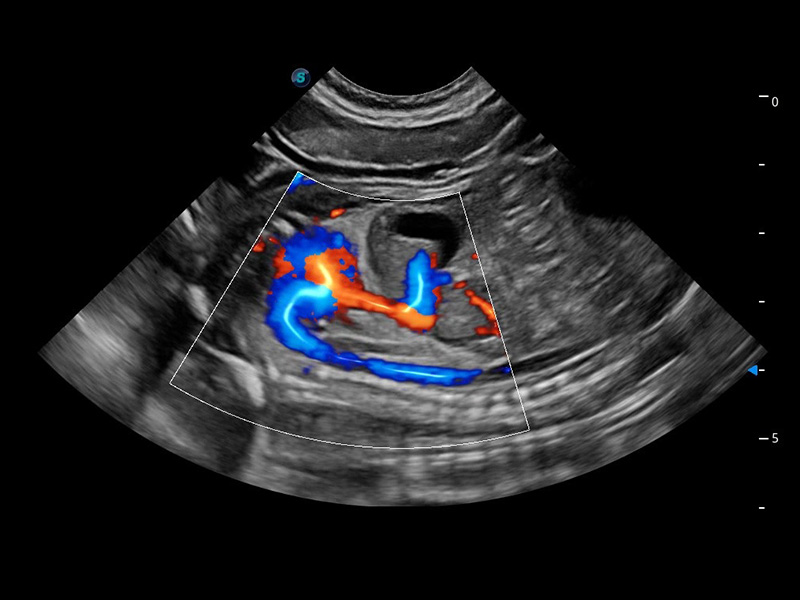

优异的基础图像

(犬)四腔心血流